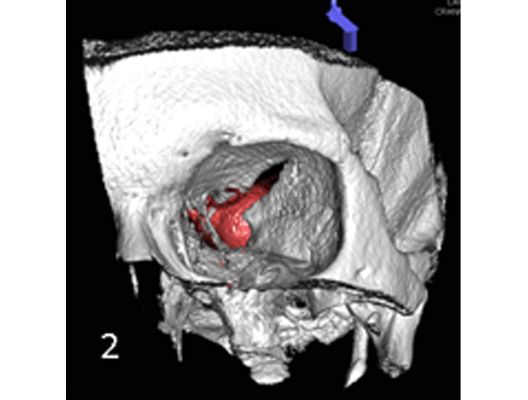

Das Beispiel zeigt die angiographischen Bilder einer Patientin, bei der es zu einer Sehstörung gekommen war. Die Ursache war ein großes Aneurysma der Halsschlagader an der Schädelbasis (Bild 1). Bild 2 zeigt die Lage des Aneurysmas hinter dem Auge. Durch den Druck des Aneurysmas auf den Sehnerv war es zu der Sehstörung gekommen. Die Patientin wurde mit einer speziellen Gefäßprothese versorgt, welche über eine Punktion der Leistenarterie in die Halsschlagader eingesetzt wurde (Bild 3). Bei der Kontrolle nach 6 Monaten zeigte sich ein vollständiger Verschluss des Aneurysmas (Bild 4). Die Sehstörung hatte sich vollständig zurückgebildet.